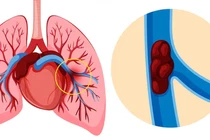

Khoa Cấp cứu, Bệnh viện Nhân Dân 115 vừa tiếp nhận và điều trị thành công một trường hợp thuyên tắc phổi nặng biến chứng sốc, đe dọa tính mạng.

Một bệnh nhân trung niên đã được Bệnh viện Quốc tế S.I.S Cần Thơ cấp cứu khẩn cấp do nguy kịch vì vỡ phình động mạch chủ ngực.